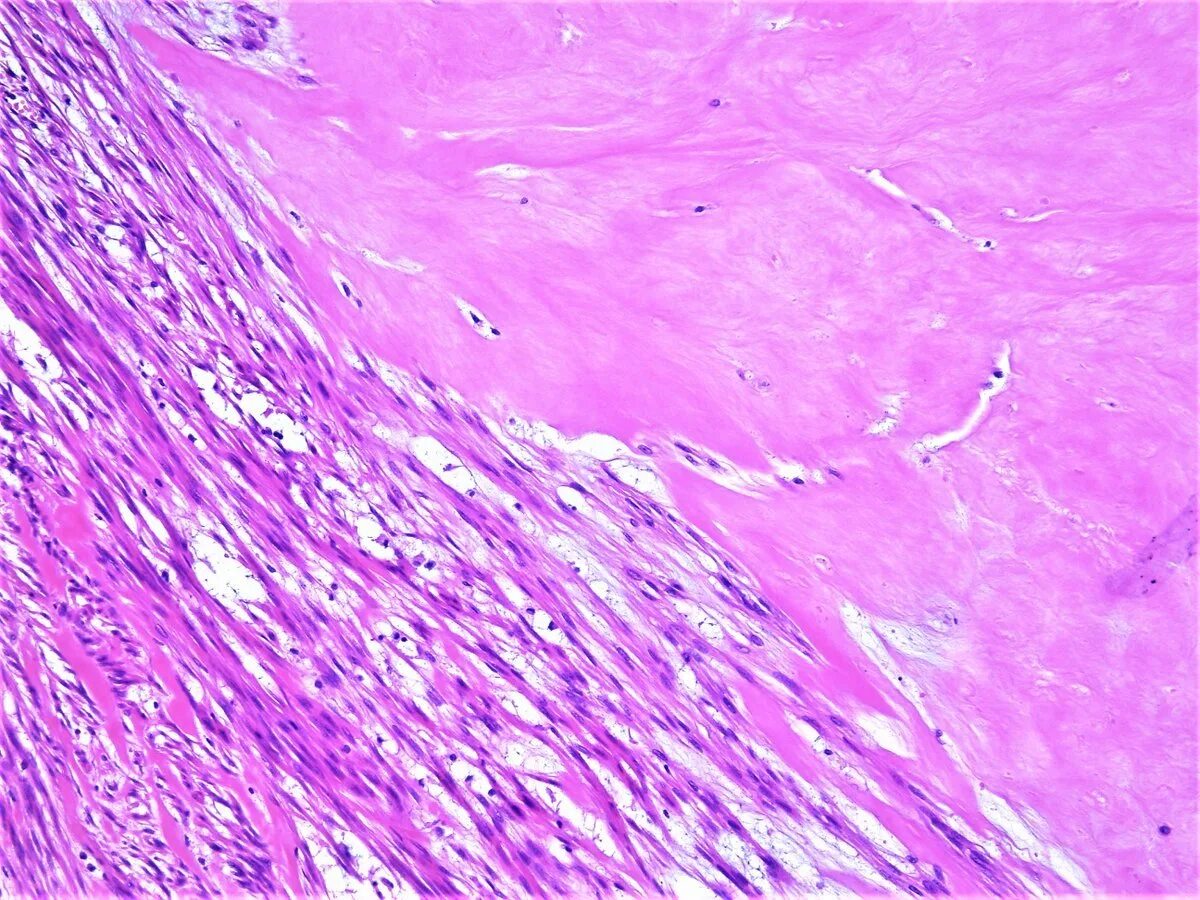

Гистология фото